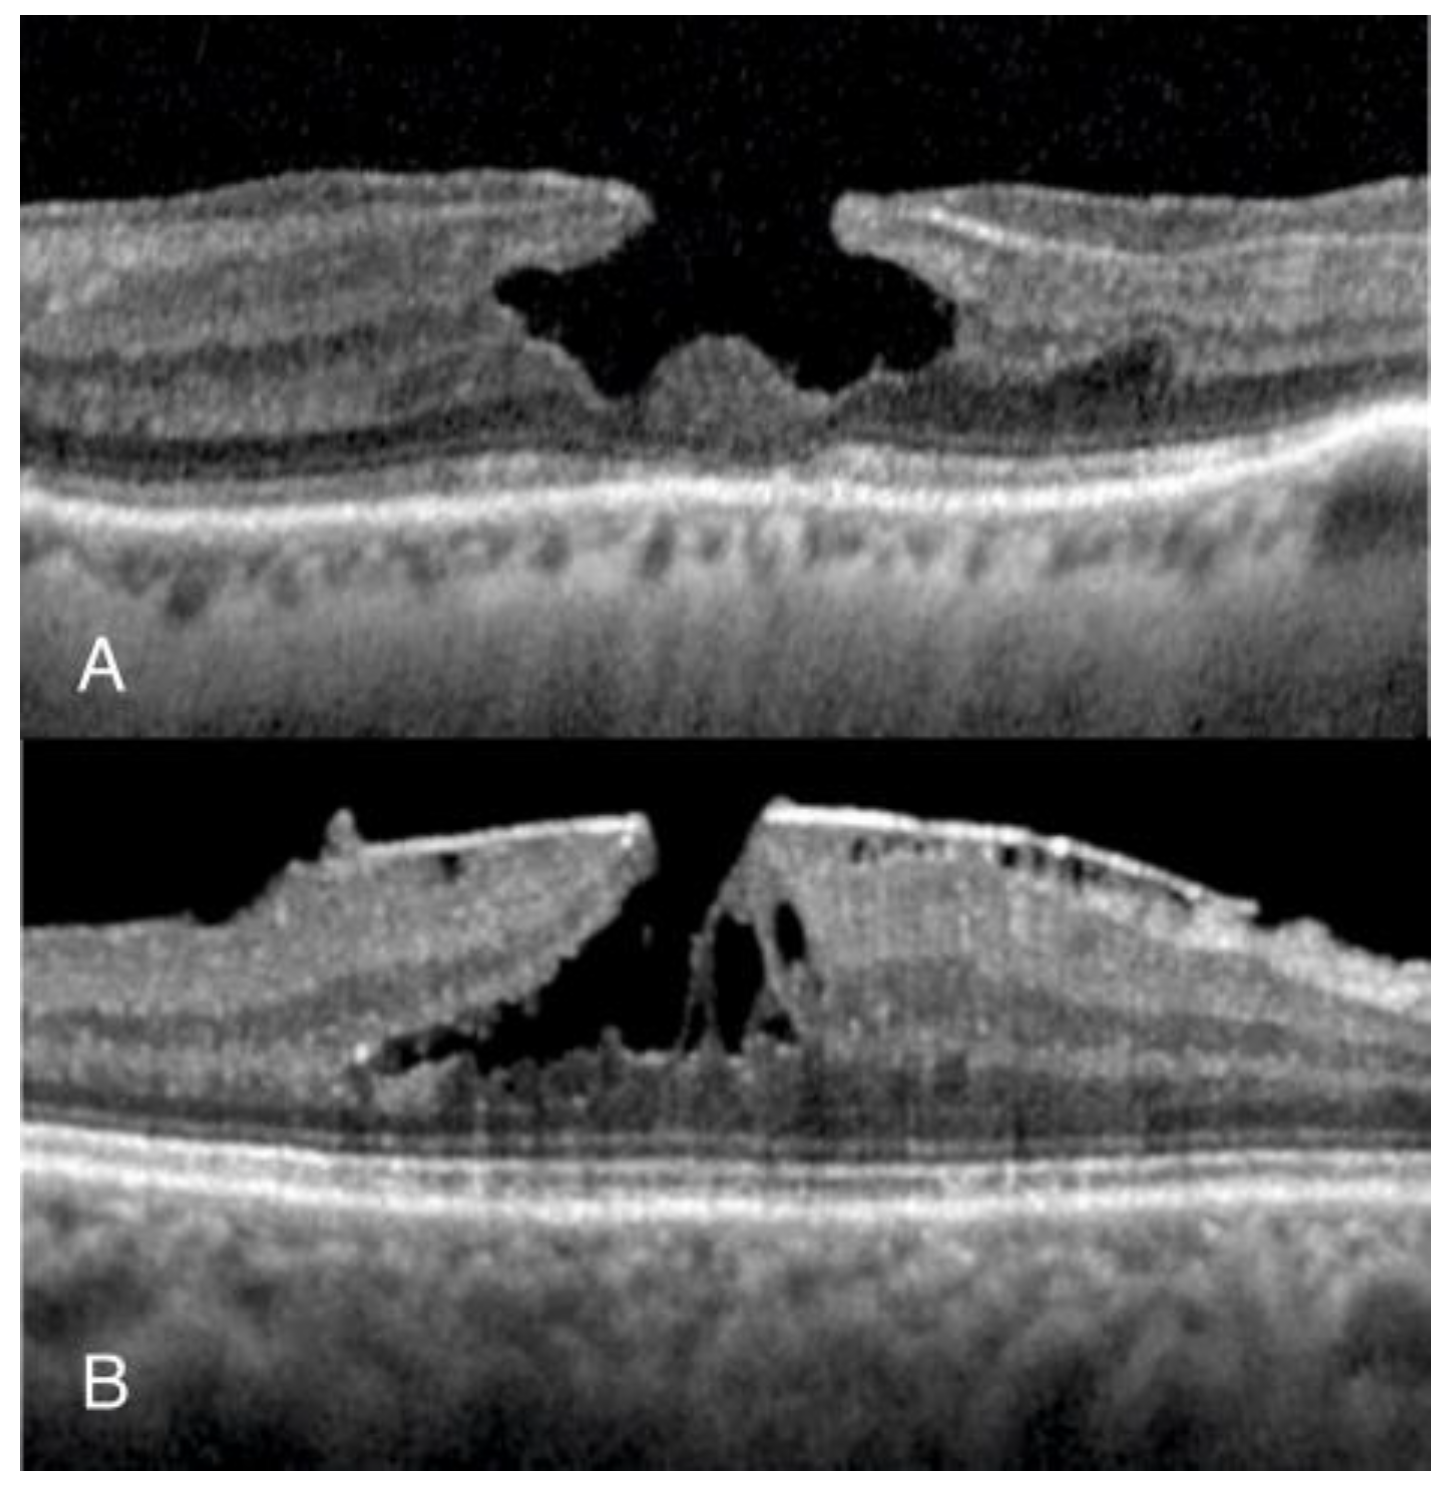

- Hubschman, J.P.; Govetto, A.; Spaide, R.F.; Schumann, R.; Steel, D.; Figueroa, M.S.; Sebag, J.; Gaudric, A.; Staurenghi, G.; Haritoglou, C.; et al. Optical coherence tomography-based consensus definition for lamellar macular hole. Br. J. Ophthalmol. 2020, 104, 1741–1747. [Google Scholar] [CrossRef]

- Moussa, G.; Jalil, A.; Lippera, M.; Alnafisee, N.; Ivanova, T. Factors influencing the reliability of measurements in eyes with full-thickness macular holes. Are we measuring incorrectly? BMJ Open Ophthalmol. 2024. [Google Scholar]